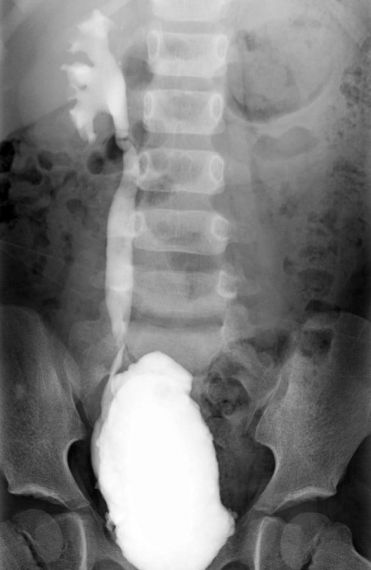

Kolor cistogram abdomena djeteta s bilateralnim vezikoureteralnim refluksom |